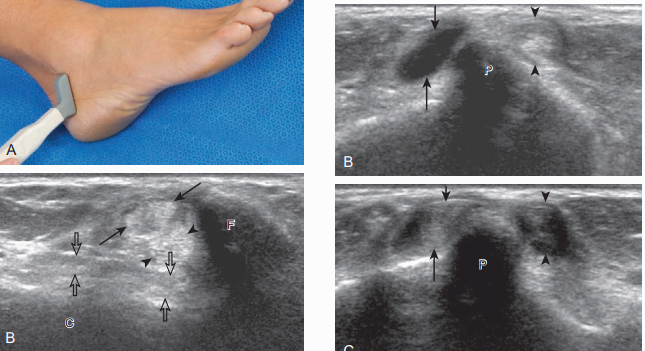

검사할 구조물은 종아리근힘줄과 가쪽인대이다. 검사는 먼저 가로면에서 가쪽복사보다 위-뒤쪽에서 시작한다. 이곳에서 짧은 종아리근의 힘살과 힘줄을 확인할 수 있다. 바로 옆에는 긴 종아리근힘줄이 있는데, 이 위치에서 긴 종아리근의 힘살은 보이지 않는다. 탐촉자를 위에서 아래로 이동하면, 짧은 종아리근 힘살이 점차 작아져서, 종아리뼈 끝에서는 두 개의 힘줄(짧은 종아리 및 긴 종아리힘줄)만 보인다. 만약 짧은 종아리근 힘살이 종아리뼈 끝보다 아래에서 보이면 이는 정상 변이로서 낮게 위치한 짧은 종아리근힘살(low lying muscle belly of the peroneus brevis)이라고 부르며 힘줄 째짐과 연관이 있기도 하다. 짧은 종아리힘줄은 종아리뼈의 뒤에 바로 붙어 있고 긴 종아리근힘줄은 짧은 종아리근보다 좀 더 뒤쪽에 있다. 얇고 높은 에코의 종아리근지지띠(peroneal retinaculum)가 힘줄을 덮고 있으며, 종아리뼈의 뒤-가쪽에 붙는다. 탐촉자를 종아리뼈의 끝 부분에서 발꿈치뼈 뒤로 비스듬히 놓으면, 발꿈치종아리인대(calcaneofibular ligament)가 종아리힘줄보다 깊은 곳에서 보인다.

가쪽 발목 검사(lateral ankle evaluation) 가로축으로 놓인 탐촉자를 종아리힘줄의 주행을 따라 세로로 추적하며 돌리면, 탐촉자는 발목의 가쪽에 관상면으로 놓이게 된다. 발꿈치뼈의 가쪽에서 '종아리결절(peroneal tubercle)'이라 불리는 뼈돌출에서 짧은 종아리힘줄과 긴 종아리힘줄은 각각 다른 방향으로 주행 경로가 나누어지며, 이곳에서는 비등방성(anisotropy) 없는 두 개의 힘줄 영상을 만들 수 없다. 따라서, 탐촉자를 시계 또는 시계 반대방향으로 돌려보면서 각각의 힘줄을 비등방성이 없는 상태로 검사한다.

종아리힘줄의 짧은 축 영상은 힘줄의 세로 째짐(longitudinal split tear)을 찾는데 적합하기 때문에 매우 중요하다. 종아리근힘줄이 종아리뼈에 대하여 가쪽 또는 앞쪽으로 탈구되는 것을 검사할 때 동적검사가 매우 유용하다. 탐촉자를 종아리뼈 뒤에 가로면으로 놓고, 환자의 발목을 뒷굽힘 또는 바깥돌림하면 힘줄 탈구를 유발할 수 있다. 이런 동적검사를 하는 도중에는 탐촉자를 너무 강하게 누르지 말아야 한다. 강하게 누르면 종아리근힘줄의 움직임을 방해할 수 있기 때문이다. 만약 종아리근지지띠가 정상이면 종아리근은 종아리뼈보다 항상 뒤쪽에 있어야 한다.